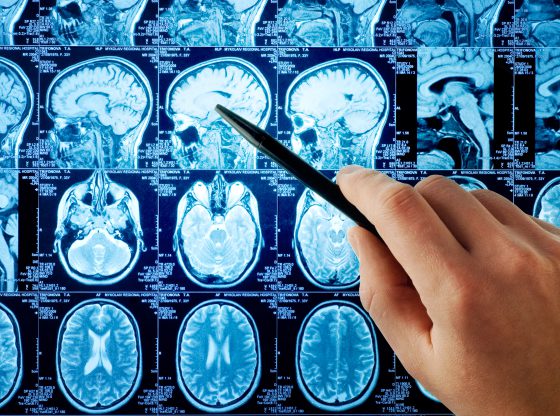

Rezonans Magnetyczny (RM) to zaawansowana technika obrazowania, która odgrywa kluczową rolę w dziedzinie medycyny. Od swojego odkrycia w latach 70. XX wieku, rezonans magnetyczny stale…